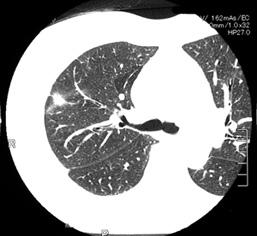

70歳代女性

健康診断で右上肺野の腫瘤陰影を指摘されてから2年間follow upしていた。徐々に腫瘤影が増大しspiculationを認めるようになる.診断と治療目的で胸腔鏡下腫瘤切除を行う。